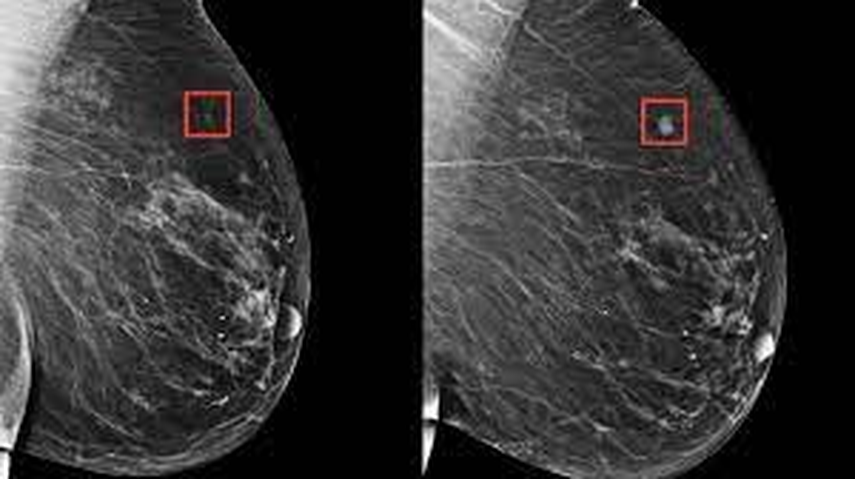

Todas ellas realizaron una mamografía, pero el primer grupo se cribó de forma convencional, es decir con la mirada de dos radiólogos independientes, mientras que los datos del segundo fueron examinados primero por una IA y luego por un solo radiólogo.

Por otra parte la tasa de "falsos positivos" los casos en los que el primer examen detecta erróneamente cáncer fue similar; el uso de esta tecnología podría reducir a la mitad la carga de trabajo de estos médicos porque el procedimiento que involucra inteligencia artificial solo necesita un radiólogo.